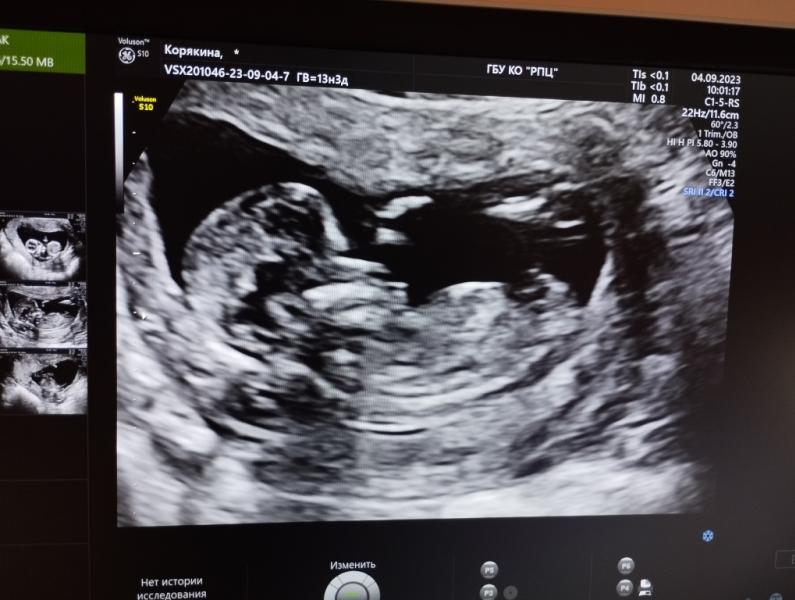

Скрининг у Кожевниковой: как все прошло, впечатления, фото малыша и предположения о поле ребенка

Была на скрининге, начиталась тут про доктора Кожевникову, боялась в кабинет идти. На деле приятная женщина, все рассказала, показала. В конце сказала что можно сделать фото с экрана. Посмотрев на малыша мне кажется у нас мальчик ❤